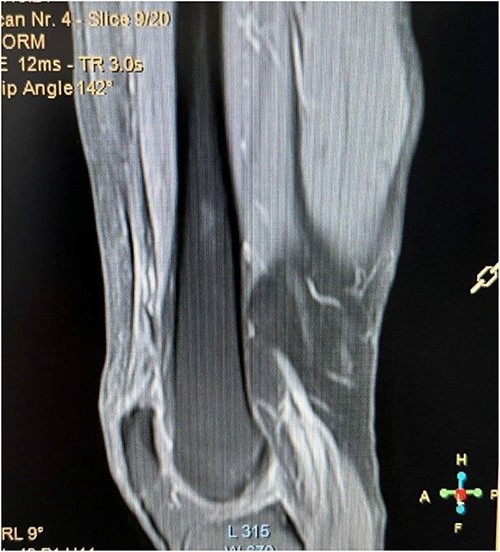

A 62-year-old male presented to emergency department of our hospital with complaints of low back pain and decrease range of motion of the right knee due to a fall from standing height. The patient was unable to weight bear and to perform a straight leg raise. His past medical history revealed no significant records. Clinical examination revealed a low back pain without neurological deficit and tenderness at right knee with a palpable defect proximal to the superior pole of the patella. Passive flexion of injured knee was measured as 110° and passive extension was full. Routine laboratory tests including white blood cells (WBC) count, erythrocyte sedimentation rate (ESR), c-reactive protein (CRP), liver and renal function were within normal ranges. The X-rays of the knee were normal without findings of patella baja and osseous pathology (Fig. 1), but the X-rays of the pelvis revealed bilateral sacroiliac arthritis. Based on this finding, further laboratory evaluation revealed a positive HLA-B27. An ultrasound scan performed externally showed a hypoechoic gap and quadriceps complete tear was noted. Magnetic resonance imaging (MRI) confirmed the findings seen on ultrasound with the difference that the rectus femoris (RF) was intact and there was a rupture of intermedius tendon (IT) combined with a partial rupture of vastus medialis. MRI sequences, especially T2W images revealed an intramuscular hematoma and discontinuity in the vastus IT (Figs 2 and 3). A small fluid filled defect, in the vastus intermedius just proximal to the insertion of quadriceps into the patella was also detected. The rectus femoris and vastus lateralis (VL) were intact. The defect in vastus intermedius measured ⁓5 cm from its patellar insertion.

Fat saturated T2 axial view showing the rupture of vastus intermedius and vastus medialis tendon.